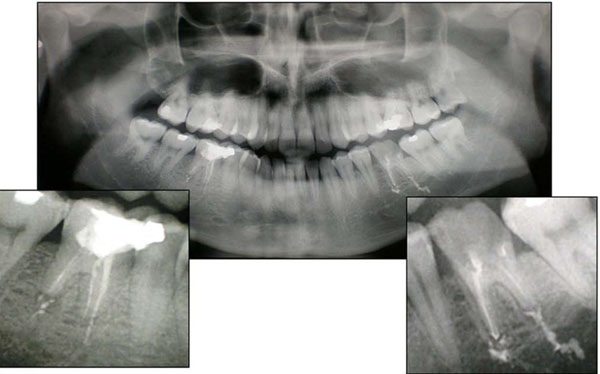

The second case concerns a patient who presented with painful symptoms corresponding to tooth the maxillary right lateral incisor. Following tests to determine pulp vitality and the absence of periodontal defects on radiological exam a diagnosis of acute pulpitis was made (Fig. 3). It was decided, therefore to begin canal therapy of the tooth concerned, followed by post-endodontic reconstruction. An orthograde endodontic treatment was carried out utilizing the warm vertical condensation technique (System B/manufacturer), with a cone of Fine-Medium gutta-percha, as well as zinc oxide/eugenol based endocanal cement (Pulp Canal Sealer/manufacturer). At his 3 month check-up, the patient complained of pain when chewing in an area most likely coinciding with the apex of the treated tooth. Examination showed there was no evidence of an area of radio-lucency in the periapical region of tooth 12 during the radiological exam, but there was slight extrusion of obturation material beyond the apex (Fig. 4).

Case 2. Pre-operative radiological exam of right lateral upper incisor (1.2) with secondary decay.

Case 2. Radiological exam of 1.2 after the first orthograde endodontic treatment with warm vertical condensation technique and apical extrusion of sealer (first dentist).

Clinical examination revealed the presence of wear facets of the crown ascribable to attrition, and so the patient was recommended for a gnatological visit. However it was decided to begin the retreatment of element 12 in order to carry out a wider shaping of the apical zone, along with prolonged irrigation in order to address any possible residual floral bacteria in the endodontic space which was responsible for the persistence of the inflammatory process [19].

The canal was closed and sealed for the second time with gutta-percha Medium and endocanal cement (Pulp Canal Sealer), using the warm vertical condensation technique. Radiological testing after another 3 months revealed no signs of periapical pathology, but the patient referred the persistence of pain (Fig. 5).

Case 2. Radiological exam after the orthograde retreatment of 1.2 with warm vertical condensation technique and apical extrusion of sealer (first dentist).

Clinical examination revealed soreness upon percussion of the tooth and a semi lunar scar in the mucosa adjacent to tooth 12. Radiological examination revealed a radiopacity at the apex of tooth 12, suggested that an amalgam had been used as the root-end filling material. There was also an area of periapical radiolucency (Fig. 6).

Case 2. Radiological exam after the first endodontic surgery and retrograde obturation with amalgam of 1.2 (second dentist).

Two months later the first dentist performed a second surgical revision of the apex by means of an intrasulcular incision creating a flap by using Velvart’s technique [20], osteotomy by ultrasonies, removal of the obturation material confirming the presence of amalgam and its scattered fragments in the bony cript. The prior resection of the apex was confirmed by the presence of a chamfer which was eliminated and followed by the preparation of the cavity using ultrasound to a depth of 3mm. The obturation material chosen was MTA (Fig. 7).

Case 2. Radiological exam after the second apicoectomy and retrograde obturation with MTA of 1.2 (first dentist).